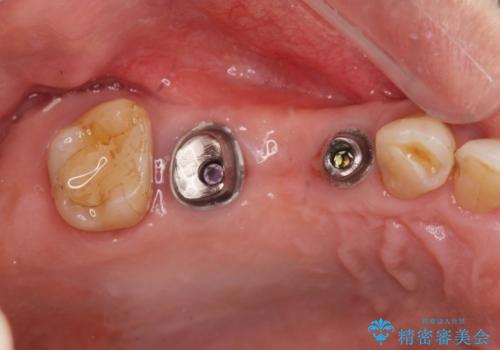

3本の歯が失われた状態を、2本のインプラントで支えるブリッジでの咬合機能回復を計画します。

- 150万円(インプラント×2・チタンカスタムアバットメント×2・ジルコニアクラウン×3・仮歯×3)費用は治療当時の料金となります